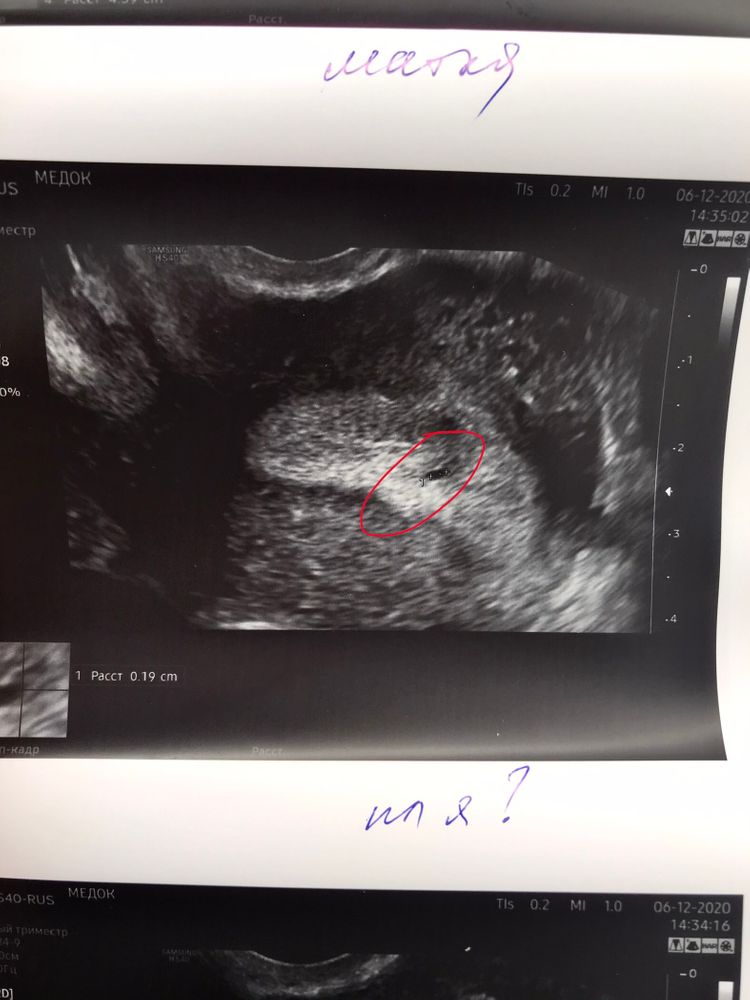

Всем доброго времени суток, дорогие девушки. Сегодня сходила на УЗИ - по моим подсчетам 5 день 5 акушерской недели(овуляция была 17 ноября, ПА 19). Фото в ответах! 😇 Все тесты уже давно с двумя полосками, сегодня хотела убедиться, что тело в матке, все в порядке. Неожиданно было обнаружено второе плодное яйцо! Подскажите, пожалуйста, у кого двойня, у вас есть так примерно выглядело? Бывало такое, что ставили то же самое, но в итоге был один малыш?) один детёныш 1,9 мм(который под вопросом), второй 2,3 мм - который точно. заранее огромное спасибо за ответы! 😘